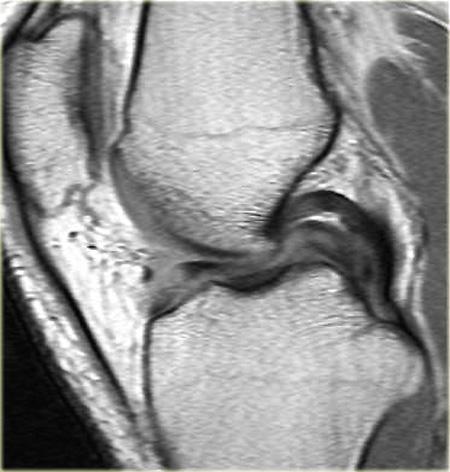

Hãy quan sát hình ảnh bên trái và cố gắng xác định vấn đề của sụn chêm này là gì.

Như bạn đã đoán được qua tiêu đề của đoạn này, đây là một trường hợp sụn chêm lật (flipped meniscus).

Sụn chêm lật là một dạng đặc biệt của rách dạng quai xô (bucket-handle tear).

Sụn chêm lật xảy ra khi mảnh vỡ của sừng sau bị lật ra phía trước, khiến sừng trước của sụn chêm có vẻ to hơn bình thường.

- Sừng sau quá nhỏ và sừng trước có vẻ to hơn với đường viền không đều.

- Thoạt nhìn có vẻ như có một đường rách dọc ở sừng trước, nhưng thực chất phần sau của cấu trúc này chính là phần lật của sừng sau bị rách.

Cấu trúc phía trước là sừng trước.

Cũng cần lưu ý tình trạng phù tủy xương khu trú và dấu ấn lõm sụn khớp. - Cấu trúc phía trước là sừng trước.